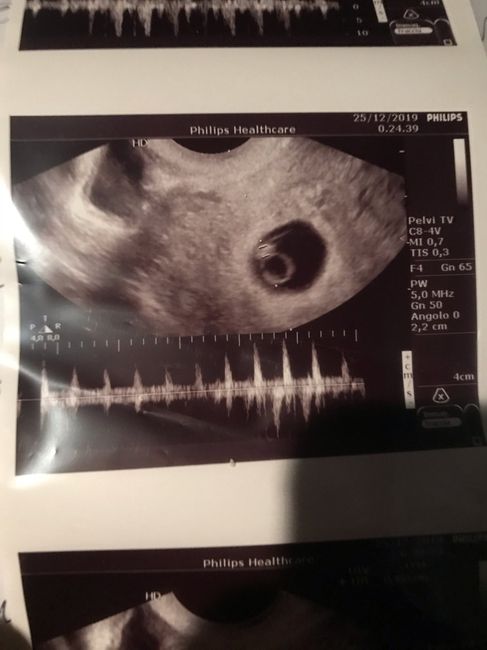

Ciao ragazze ho bisogno di voi, sto passando giorni di pura ansia e sarà così fino la prossima visita cioè l’8. Vi racconto la mia esperienza e spero che qualcuno mi possa aiutare. Ho fatto la prima visita a 7 settimane e si vedeva solo la camera e...